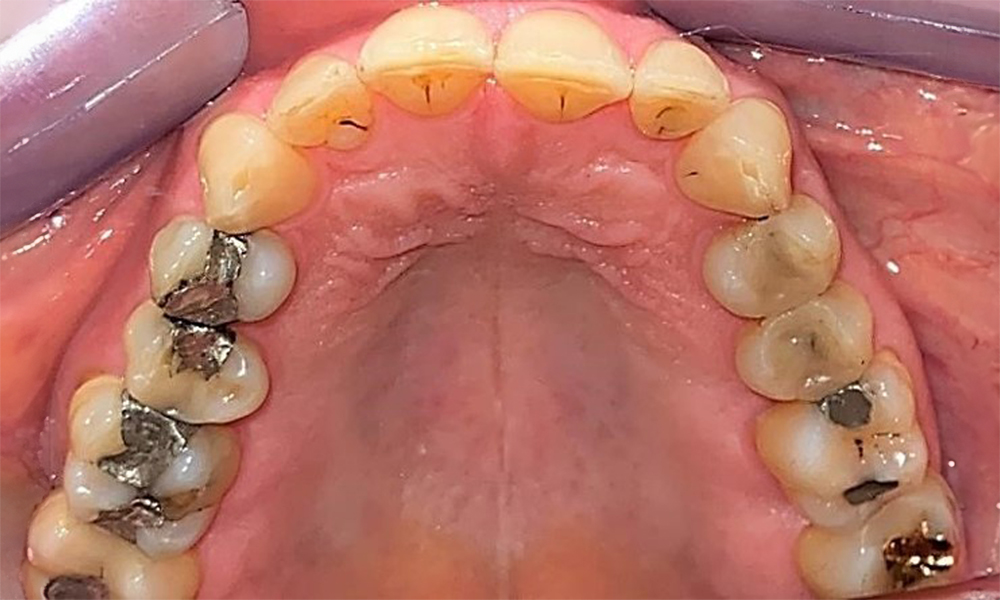

Occlusal view of the mandible showing the denture in situ.

Fig. 6 Occlusal view of the mandible showing the denture in situ. © Dr R. Krapf

The patient has a full dentition with 28 teeth, which includes amalgam and composite fillings in the molar and premolar regions. There is a visible clinical marginal gap present on tooth 14. Tooth 27 has an adequate gold inlay. There are also generalized attritions and abrasions. (Fig. 2, Fig. 3, Fig. 4, Fig. 5, Fig. 6)